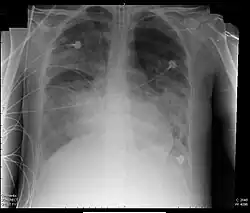

Verletzungen der Lunge können neben einer Lungenkontusion als Quetschverletzung Lungenrisse sein. Letztere führen zu einem Pneumothorax, wie er bei 10 bis 50 Prozent der Patienten mit Thoraxtrauma auftritt,[6] und gegebenenfalls zu einem Spannungspneumothorax. Blutungen in den Thorax hinein führen zu einem Hämatothorax. Bei einem Hämatopneumothorax treten sowohl ein Pneumo- als auch ein Hämatothorax in Kombination auf. Symptome sind zunächst Luftnot und je nach Ausmaß der Blutung auch Kreislaufinstabilität. Bei einem Pneumothorax kann sich insbesondere bei Ausbildung eines Spannungspneumothorax ein Hautemphysem bilden, das eine große Ausdehnung erreichen kann. Therapie ist eine Entlastung der Pleurahöhle mittels Thoraxdrainage auf der betroffenen Seite. Üblicherweise kommen kleinere intrathorakale Blutungen von alleine zum Stehen, so dass außer einer Drainage keine weiteren Maßnahmen notwendig werden. Eine Thorakotomie zur operativen Blutstillung kann bei einem initialen Blutverlust von mehr als 1.500 ml nach der Thoraxdrainage oder bei einem fortwährenden Blutverlust von mehr als 250 ml pro Stunde über mehr als vier Stunden erfolgen.[2][5]

Hämodynamisch stabile Patienten mit penetrierenden Thoraxverletzungen bedürfen neben einer Thoraxdrainage zunächst keiner weiteren Akutmaßnahmen. Neben weiterer Diagnostik steht hier eine klinische Verlaufskontrolle im Vordergrund, da unerkannte kleinere Blutungen oder Verletzungen intrathorakaler Organe verzögert klinisch wirksam werden können.[2]